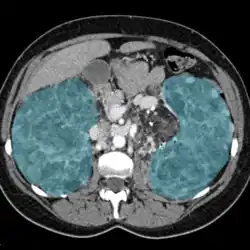

Enlarged kidneys in blue

Nephromegaly is the process whereby one or both kidneys become enlarged. It is defined as an enlargement of more than two standard deviations above the mean for age and body size of a particular individual. It can be caused by a variety of conditions including infiltrative disorders, metabolic conditions, cysts, and other diseases.

Nephromegaly is the process whereby one or both kidneys become enlarged.[2] It is defined as an enlargement of more than two standard deviations above the mean for age and body size of a particular individual. In adults, as the normal kidney length is typically 10–12 cm (3.9–4.7 in), lengths above 13 cm (5.1 in) suggest a general enlargement.[3][4]

A pelvic ultrasonography is used for visualizing the kidneys, and detecting their size, structure, and presence of edema, and cysts. Further imaging such as Computer Tomography, Magnetic Resonance Imaging, and PET-CT can assess masses and structural anomalies. Blood tests and biopsies may be required for further analysis.[15]